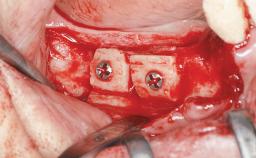

Iliac and Calvarial Bone Blocks for Onlay Grafting of a Severely Resorbed Edentulous Maxilla

Bone Augmentation Horizontal|Sinus Floor Elevation|Staged|Vertical

Augmentation Materials Autogenous chips|Autogenous block(s)